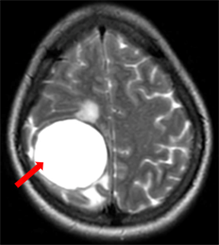

Ca lâm sàng: Chẩn đoán ung thư tuyến giáp di căn não tại Trung tâm Y học hạt nhân và Ung bướu, bệnh viện Bạch Mai Ngày đăng: 30/01/2026 Ung thư tuyến giáp (UTTG) là loại ung thư phổ biến nhất trong các ung thư của hệ thống tuyến nội tiết, với tỷ lệ mắc có xu hướng gia tăng trong những năm gần đây. Theo GLOBOCAN 2022, UTTG đứng hàng...